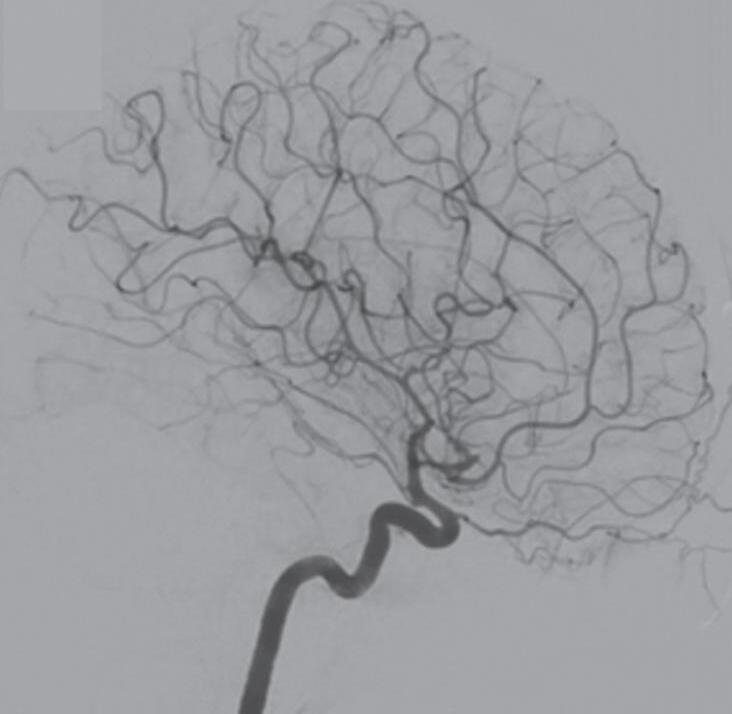

Com relação ao fluxo no interior do nidus, alguns autores classificam-nas em alto fluxo (Fig. 1-8) e baixo fluxo (Fig. 1-9). São consideradas de alto fluxo aquelas em que a opacificação após injeção de contraste ocorre apenas na malformação, em contrapartida, nas de baixo fluxo, ocorre opacificação da MAV e de outras artérias normais do mesmo território vascular. Exemplificando as lesões de alto fluxo temos as malformações arteriais, as malformações arteriovenosas e as fístulas arteriovenosas, enquanto as lesões de baixo fluxo são representadas pelas malformações venosas, linfáticas e capilares.25

Fig. 1-8. (a-c) RNM T1 com contraste, cortes sagital (a), coronal (b) e axial (c) demonstrando MAV não rota com nidus localizado no lobo occipital à esquerda (setas longas). (d) Arteriografia digital cerebral com injeção de contraste via carótida direita (AP) mostrando a contribuição da carótida direita na irrigação da MAV contralateral. (e,f) Com injeção de contraste via carótida esquerda, em Perfil e AP respectivamente, observa-se nidus compacto nutrido por ramos da artéria cerebral média à esquerda e a veia de drenagem precoce se dirigindo para o seio sagital superior. Projeções em AP (g) e em perfil (h) demonstrando a contribuição do sistema vertebrobasilar por meio de ramos distais da artéria cerebral posterior à esquerda e drenagem para os seios sagital superior e sigmoide à esquerda (setas curtas).